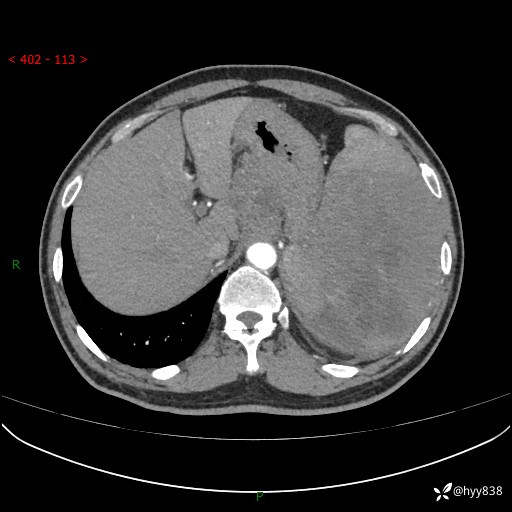

上腹部CT平扫

增强(动脉期+静脉期)